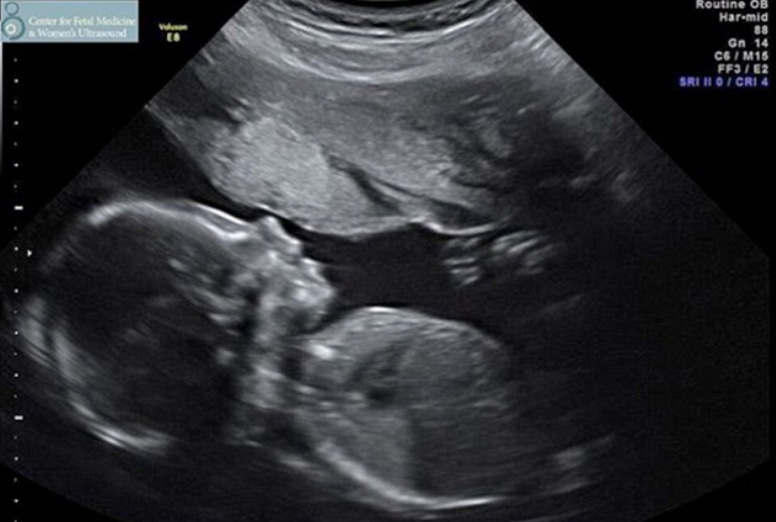

Летом 2018 года специалист по развитию бизнеса American Addiction Centers в Лос-Анджелесе Варуни Вонгсвираты заявила, что ждет ребенка от 49-летней голливудской звезды. Она опубликовала в Сети снимок УЗИ и сообщила, что девочка родится осенью. Актер потребовал сделать ДНК-тест.